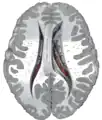

Central part and anterior and posterior cornua of lateral ventricles exposed from above.